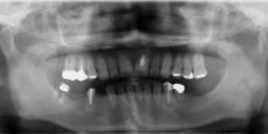

臼歯部3本インプラントを適用した症例

下顎臼歯部両側インプラント補綴

両側臼歯部欠損に対しインプラント補綴をインフォームドコンセントにより患者様がご選択されたので3本のインプラント治療を行った。インプラント埋入を行い安静期間を経て上部構造をジルコニアセラミックで製作し装着した。

施術の価格

臼歯部インプラント3本合計937500円